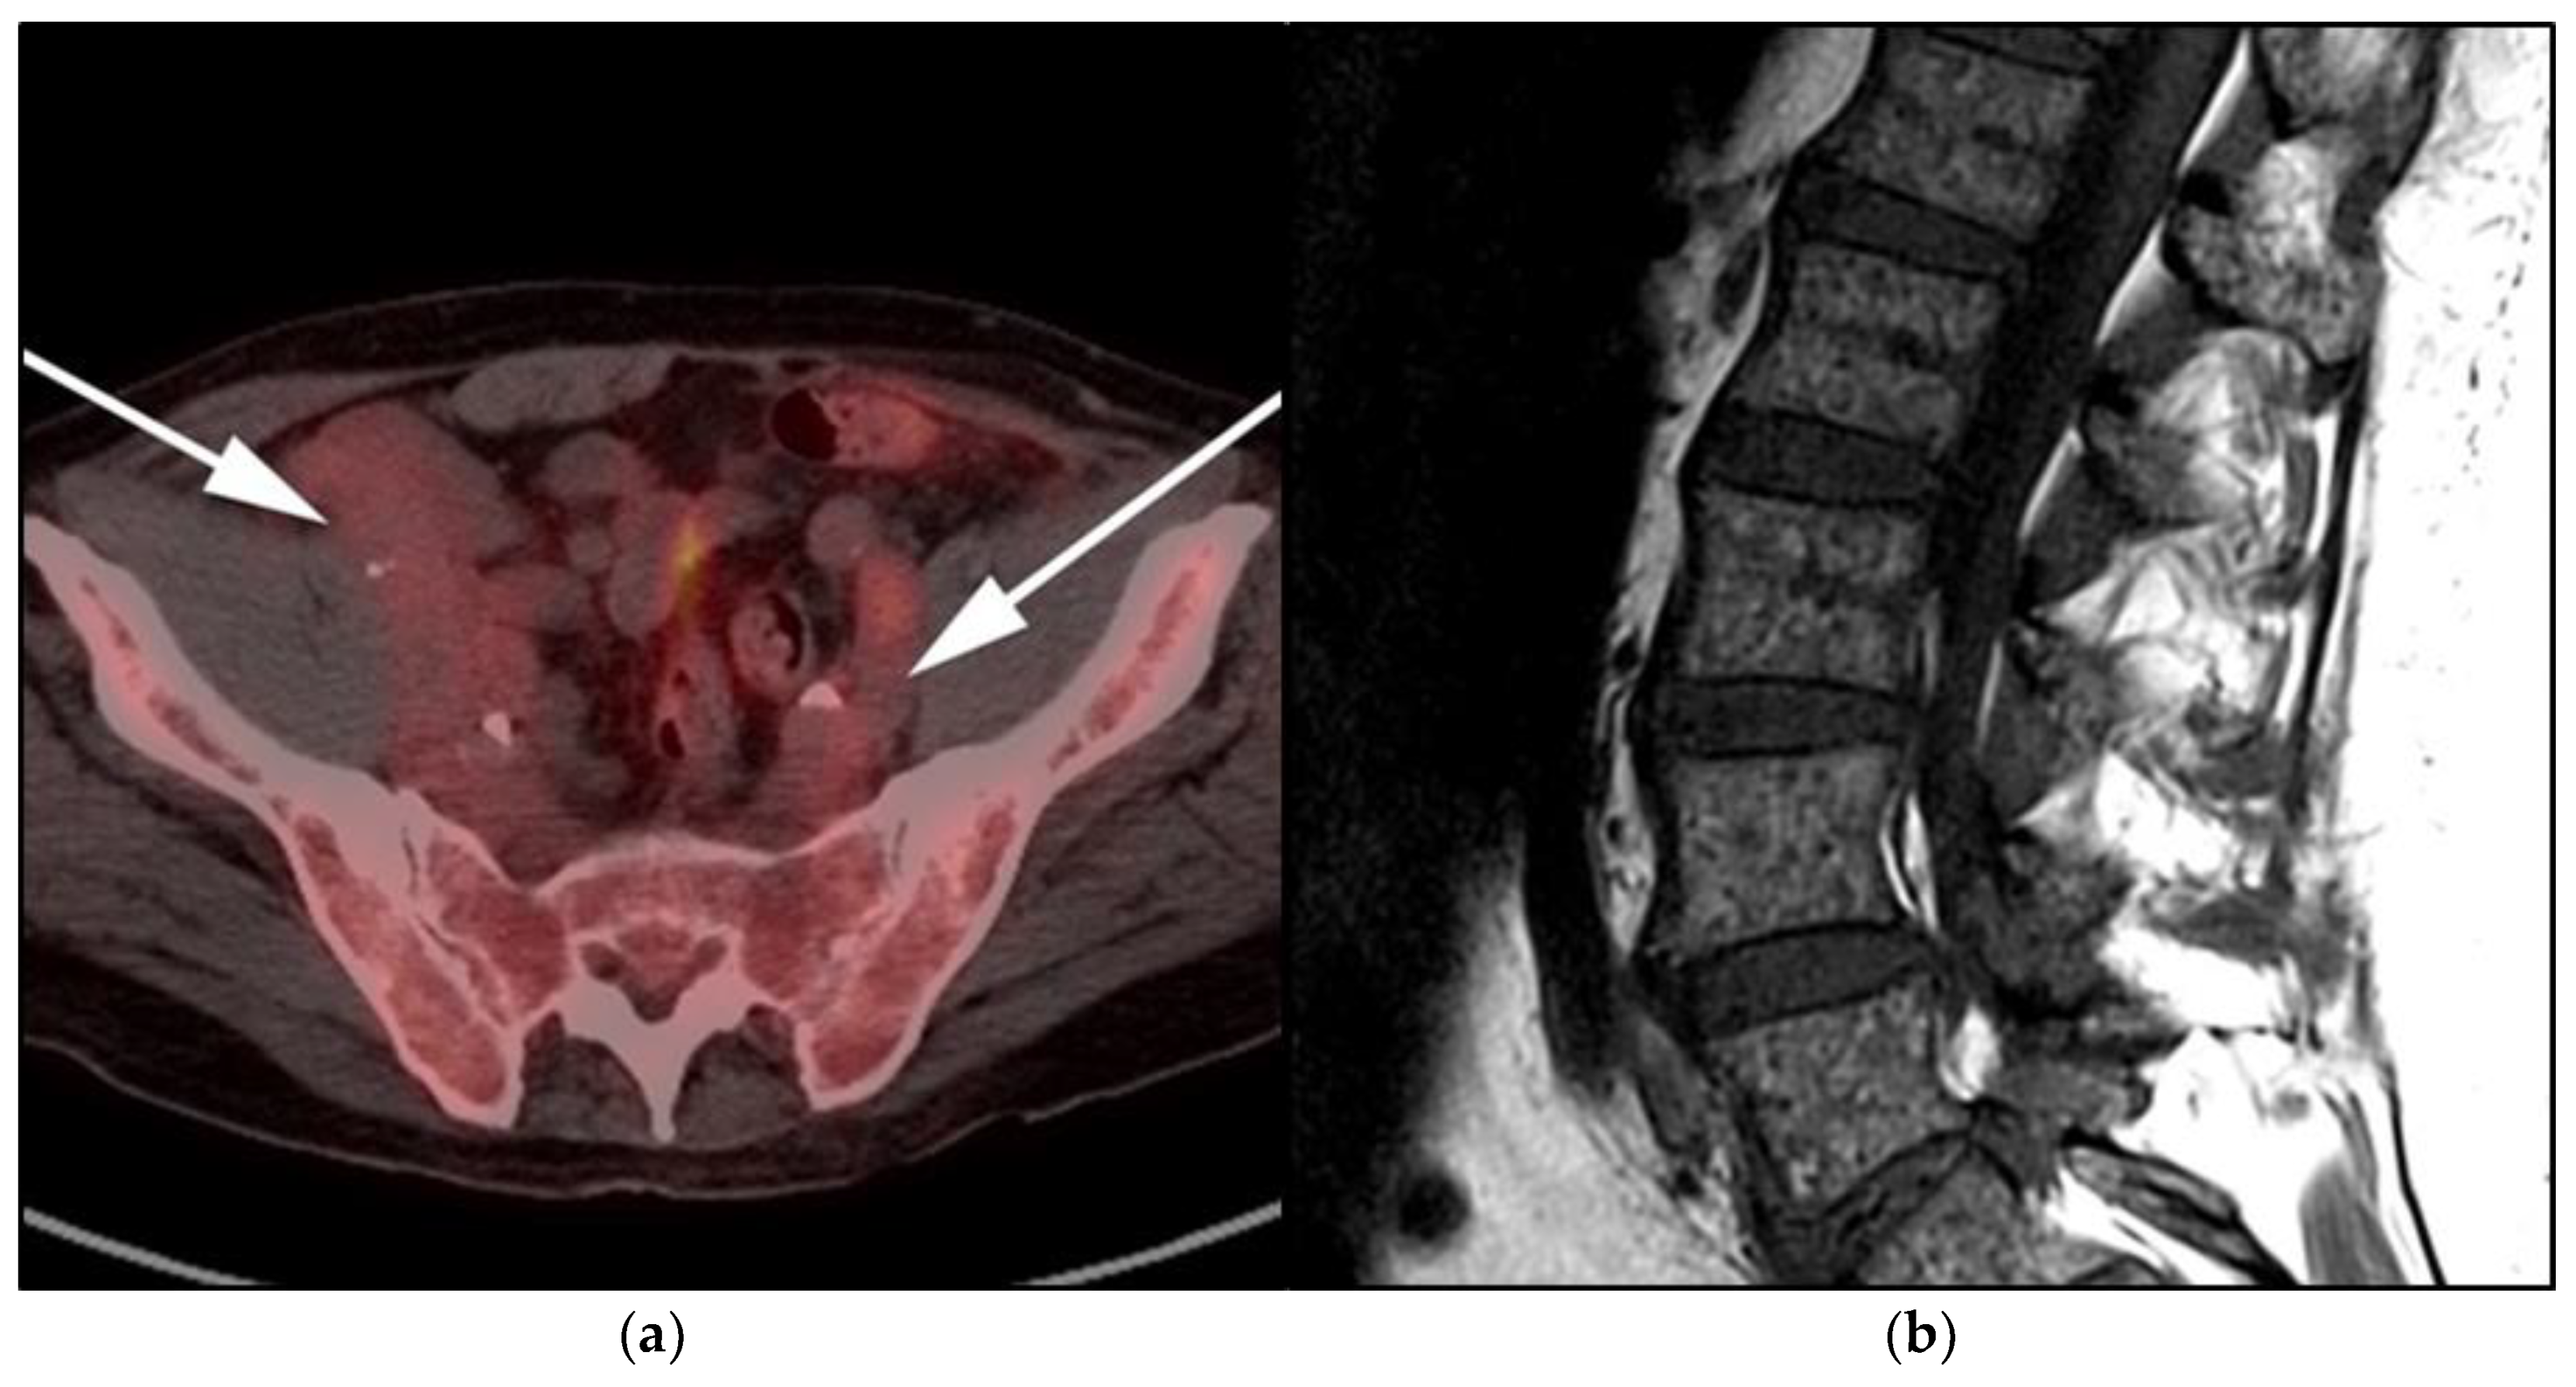

Imaging is not necessary to establish a diagnosis of ALPS but might aid in its diagnostic evaluation. Stability in the size of lymphadenopathy and hepatosplenomegaly over many years may suggest ALPS from other malignant lymphoproliferative diseases [26] (Figure 4).

Figure 4.

A 30-year-old male with known history of autoimmune lymphoproliferative disorder since childhood. (a) Maximal intensity projection (MIP) FDG PET/CT image shows generalized hypermetabolic lymphadenopathy throughout the head, neck, chest, abdomen, and pelvis (white arrows). Note that splenic activity is not visualized (thin white arrow) because the spleen was surgically removed during childhood due to splenomegaly. (b) Axial FDG PET image shows hypermetabolic adenopathy within pelvis mainly about the bilateral pelvic side wall and external iliac nodes (white arrows). Lymph nodes often show little or only modest uptake, a clue, in addition to stability of nodal size and over multiple time points. Biopsy is the only method for definitive diagnosis. (c) H&E section of a lymph node shows highly proliferative paracortical expansion composed of small proliferative lymphocytes and immunoblasts with preserved lymphoid follicular architecture. There is sinus histiocytosis. (Original magnification 400×, H&E stain).

Once the diagnosis of ALPS is established, baseline and periodic follow-up CT scans should therefore be obtained to document the stability of lymphadenopathy and hepatosplenomegaly. 18F-FDG PET/CT may also be helpful because mild to moderate FDG uptake is typical of ALPS compared to the high FDG uptake characteristic of malignant lymphomas. By evaluating for areas of high FDG uptake, 18F-FDG PET/CT may help in the early detection of lymphoma transformation and demonstrate the best site for biopsy, when indicated [23]. Awareness of ALPS is pivotal because ALPS often requires long-term immunosuppressive therapies as opposed to chemotherapy that is standard for malignant lymphoproliferative disorders.